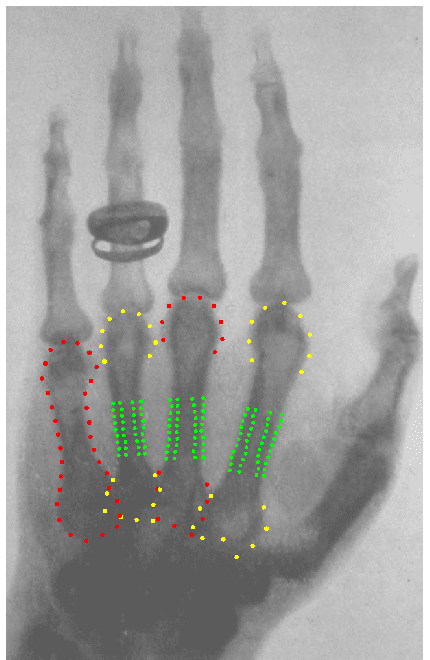

The Swiss anatomist Albert von Kölliker volunteered to have his hand X-rayed during the lecture, and the resulting image has now been analysed with a new version of BoneXpert, presented in the Archives of Osteoporosis

The new method automatically measures the cortical thickness in the three middle metacarpals and was developed in cooperation with Jena and Copenhagen universities. Reference curves for four indices of cortical bone were determined for males and females up to the age of 90 based on a large cohort of healthy subjects from Jena.

The metacarpal index of 78-year old Albert von Kölliker was found to be 0.634, which translates into a Z-score of 2.4. We conclude that his bone health was far above normal.

- The Metacarpal Index: MCI ∼ T / W. This works even if the image magnification is unknown as was the case for von Kölliker